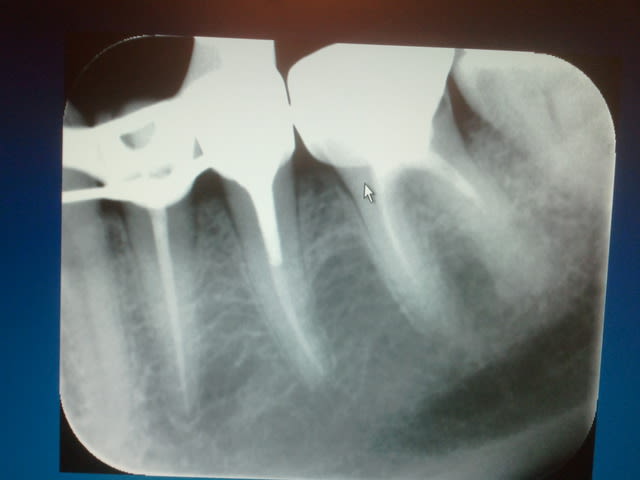

Radio cone en place avant obturation, j'ai rarement un problème avec le mv2 avec lequel soit je n'arrive pas à l'apex soit je bute sur la paroi du mv1 si ceux ci sont en y. Jamais de cathétérisme manuel seulement une localisation d'apex au S1 protaper sur endomaster, repère visuel sur les graduations puis r25. récapitulation en plusieurs fois si les instruments forcent toutefois. Je vais essayer la localisation au gold pour voir si ca dit la meme chose que l'endo master. Ci dessous l'endo molaire du jour c'est tout frais (en général je poste les endos de la journée) ici en l'occurrence patient vu pour la premiere fois, status radio + endo 45 mn.

La pèche a été bonne sur le status endo sur 45 à suivre.))))))

Superbe endo !! Tu ne reconstitues pas en systématique tes dents avant endo ( cavité distale sur RX)?Tu ne fais donc jamais de radio lime en place avant préparation des canaux? Ta longueur de preparation est-elle toujours correcte? Jamais de faux positifs? Tu utilises la localisation uniquement avec l'endomaster et non le reciproc?

Ca c'est cones en place))))), la cavité distale ne m'a pas dérangée dans ce cas (digue bien plaquée en distal et étanche) , sinon oui je fais une reconstitution pré endo si il y a des fuites.

Jamais de limes en place (j'en ai pas) localisation au s1 sur endo master uniquement puis éventuellement avec un mtwo 25 à la fin pour être sur d'être à l'apex en 25 -06 (une formalité).